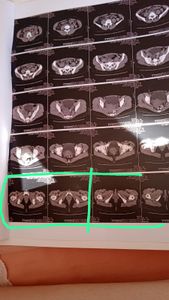

Eu  sou Tatiany Costa Santos, tenho  31 anos e  03 filhos. Fui diagnóstica com problemas nos dois rins, e alertada pelo médico que posso perdê-los não posso esperar  pelo SUS.  O valor da cirurgia fica em R$10.000,00. Não tenho condições de custear, peço a sua contribuição  através desta campanha. Que  Deus os dê em dobro tudo que me ajudar. Gratidão,  desde já!